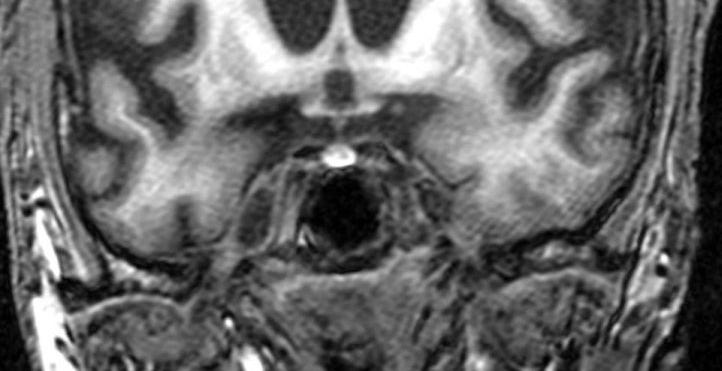

Magnetkamerabild av en patient med Huntingtons. (Picasa 2.6)